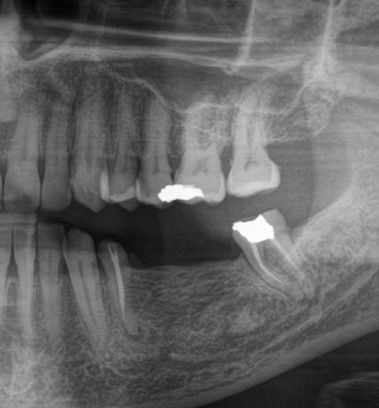

The radiographic evaluation showed images compatible with periodontal ligament widening, root canal treatments and periapical lesions on teeth #34 and #37. Furthermore, vertical bone availability was observed (Fig. 3).